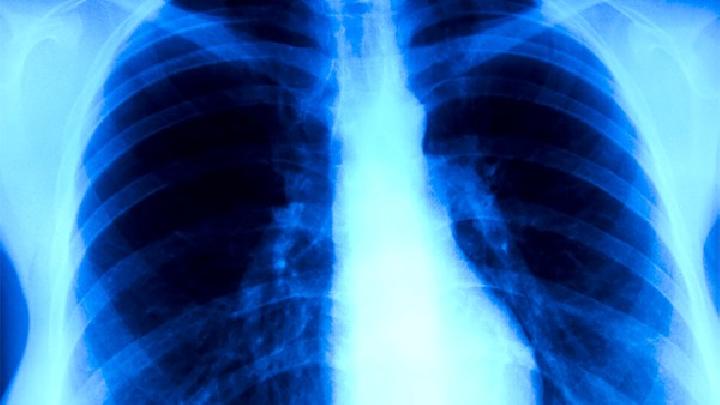

肺炎一般都会有胸部刺痛,一般都是咳嗽或者呼吸的时候最明显。我们还可以从很多肺炎的症状看出,下面就让权威专家来为我们解说下,希望阅读完本文能够对您有所帮助。

肺炎的症状包括以下几点:

1、病毒性肺炎的起病缓慢,头痛、乏力、肌肉酸痛、发热、咳嗽、干咳或少量黏痰,流感病毒肺炎开始为典型的流感症状,12—36小时内,呼吸增快,进行性呼吸困难、紫绀,可发生呼吸衰竭及休克,两肺可闻及湿罗音或哮鸣音,这是肺炎的症状。

2、病菌性肺炎的起病急骤,肺炎的症状通常有高热,体温在数小时内可上升至39℃-40℃。胸部刺痛,随呼吸和咳嗽加剧。咳嗽,咳铁锈色或少量脓痰。常伴有恶心、呕吐,周身不适和肌肉酸痛。

其肺炎的症状和体征可因感染病菌的不同而有所差别。

3、吸人性肺炎为液体、颗粒性物质或分泌物进入下气道引起。多见于久病卧床的肺炎患者。如吸入量大,可引起急性肺损伤或阻塞远端的反复感染出现急性呼吸困难,呼吸急促及心动过速或发热、咳嗽、咳痰等类似细菌性肺炎的症状。

以上就是关于肺炎的症状的介绍。如果您在日常生活中发现了以上多种症状的话,那么您就有可能是患了肺炎,为了您的健康,最好的办法就是去医院进行检查,早日检查,早日恢复健康,谢谢您对本站的支持与信任。